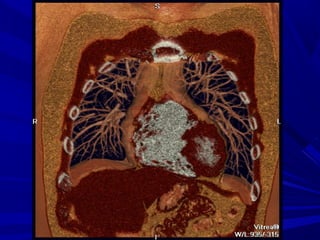

A diagnosis of PE is established

on the basis of individual

transverse sections, although,

extensive or

isolated PE,

as well as normal pulmonary

vasculature can be visualized by

means of 3D reconstructions.

Extensive

acute

central PE

with "saddle

embolus"

extending

into both

central

pulmonary

arteries.